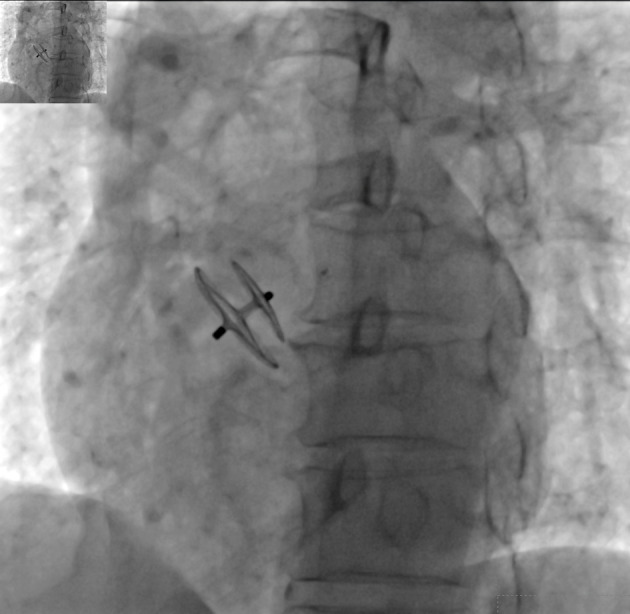

Abstract Image